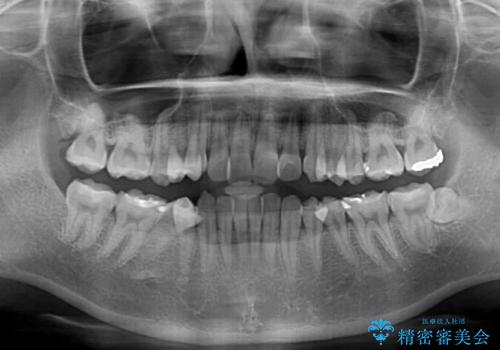

- 上下前歯のデコボコ、特に右上の八重歯を気にして来院された患者様です。

事前に親知らずを抜歯しておき、出産時期に困ることのないように準備をした上で治療を開始しました。